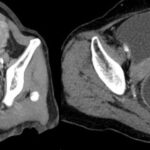

Se presenta el caso de una paciente femenina de 71 años, que ingresa por guardia con dolor abdominal en fosa iliaca derecha y deposiciones diarreicas sanguinolentas. Al examen físico, abdomen blando depresible, con masa palpable, y doloroso a la palpación en FID. En la TC de abdomen y pelvis con contraste oral y EV se observó el pasaje del contraste oral hasta colon derecho. Ángulo derecho descendido de topografía, donde se observa área redondeada de engrosamiento parietal con realce. Distalmente se observa intususcepción, que compromete el resto de colon hasta el recto con ligero realce parietal en dichos segmentos en relación con hiperemia. No se observó dilatación de asas delgadas.

En la TC de abdomen y pelvis con contraste oral y EV se observó el pasaje del contraste oral hasta colon derecho. Ángulo derecho descendido de topografía, donde se observa área redondeada de engrosamiento parietal con realce. Distalmente se observa intususcepción que compromete el resto del colon hasta el recto, con ligero realce parietal en dichos segmentos en relación con hiperemia. No se observa dilatación de asas delgadas.